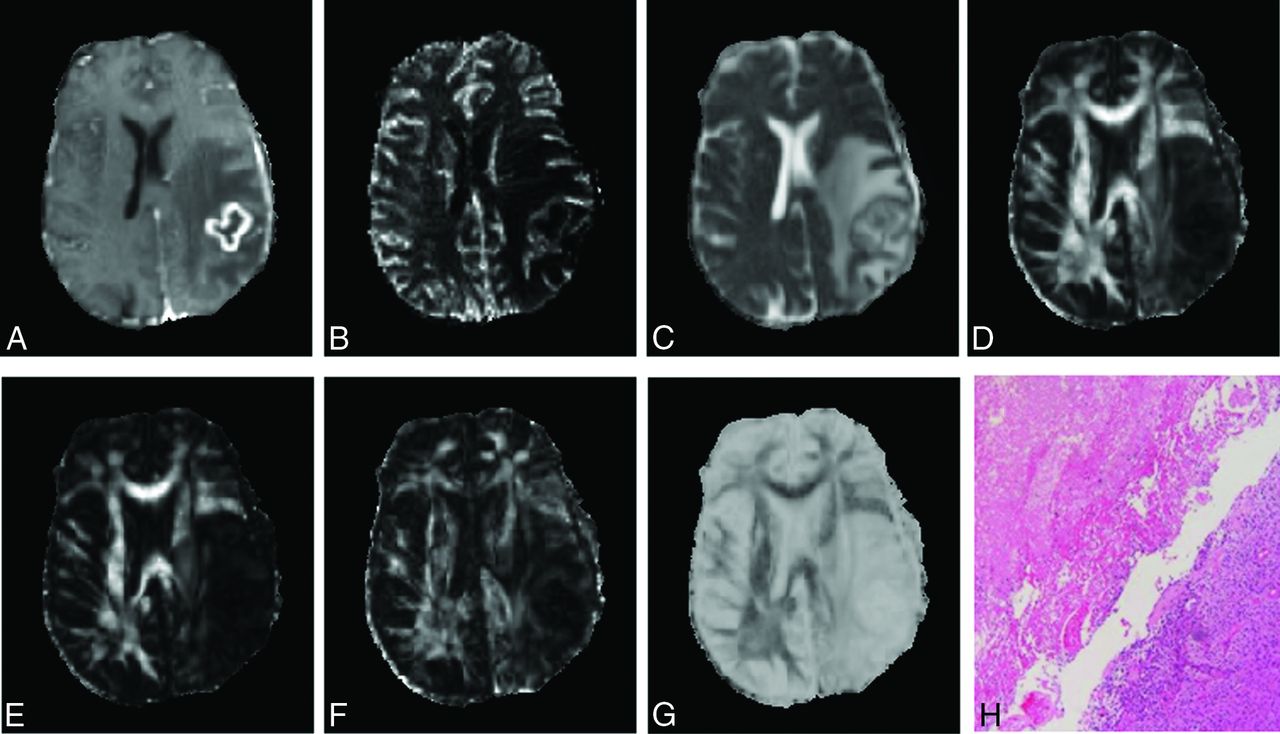

Representative MR images and histologic photomicrographs from patients with PsP, mixed, and TP features are shown in Figs 1⇓–3, respectively. MD maps demonstrate variable degrees of diffusivity from the enhancing parts of the tumor. Anisotropy and rCBV maps also show variability. However, quantitative analysis revealed significantly higher median FA, CL, and CP values and higher rCBV in patients with TP compared with PsP and mixed response (Fig 4).

Axial MR images of a 44-year-old man with PsP. Contrast-enhanced T1-weighted image (A) shows a new enhancing lesion in the left parietal lobe. CBV map (B) shows moderately increased CBV from the lesion. MD (C) looks similar to the normal white matter. Decreased FA (D), CL (E), and CP (F) and increased CS (G) are observed from the enhancing part compared with normal white matter. Photomicrograph of a histologic section (H, hematoxylin-eosin stain, 50× magnification) reveals most of the tissue with treatment-related changes, including extensive geographic necrosis and vascular fibrinoid necrosis (90%).